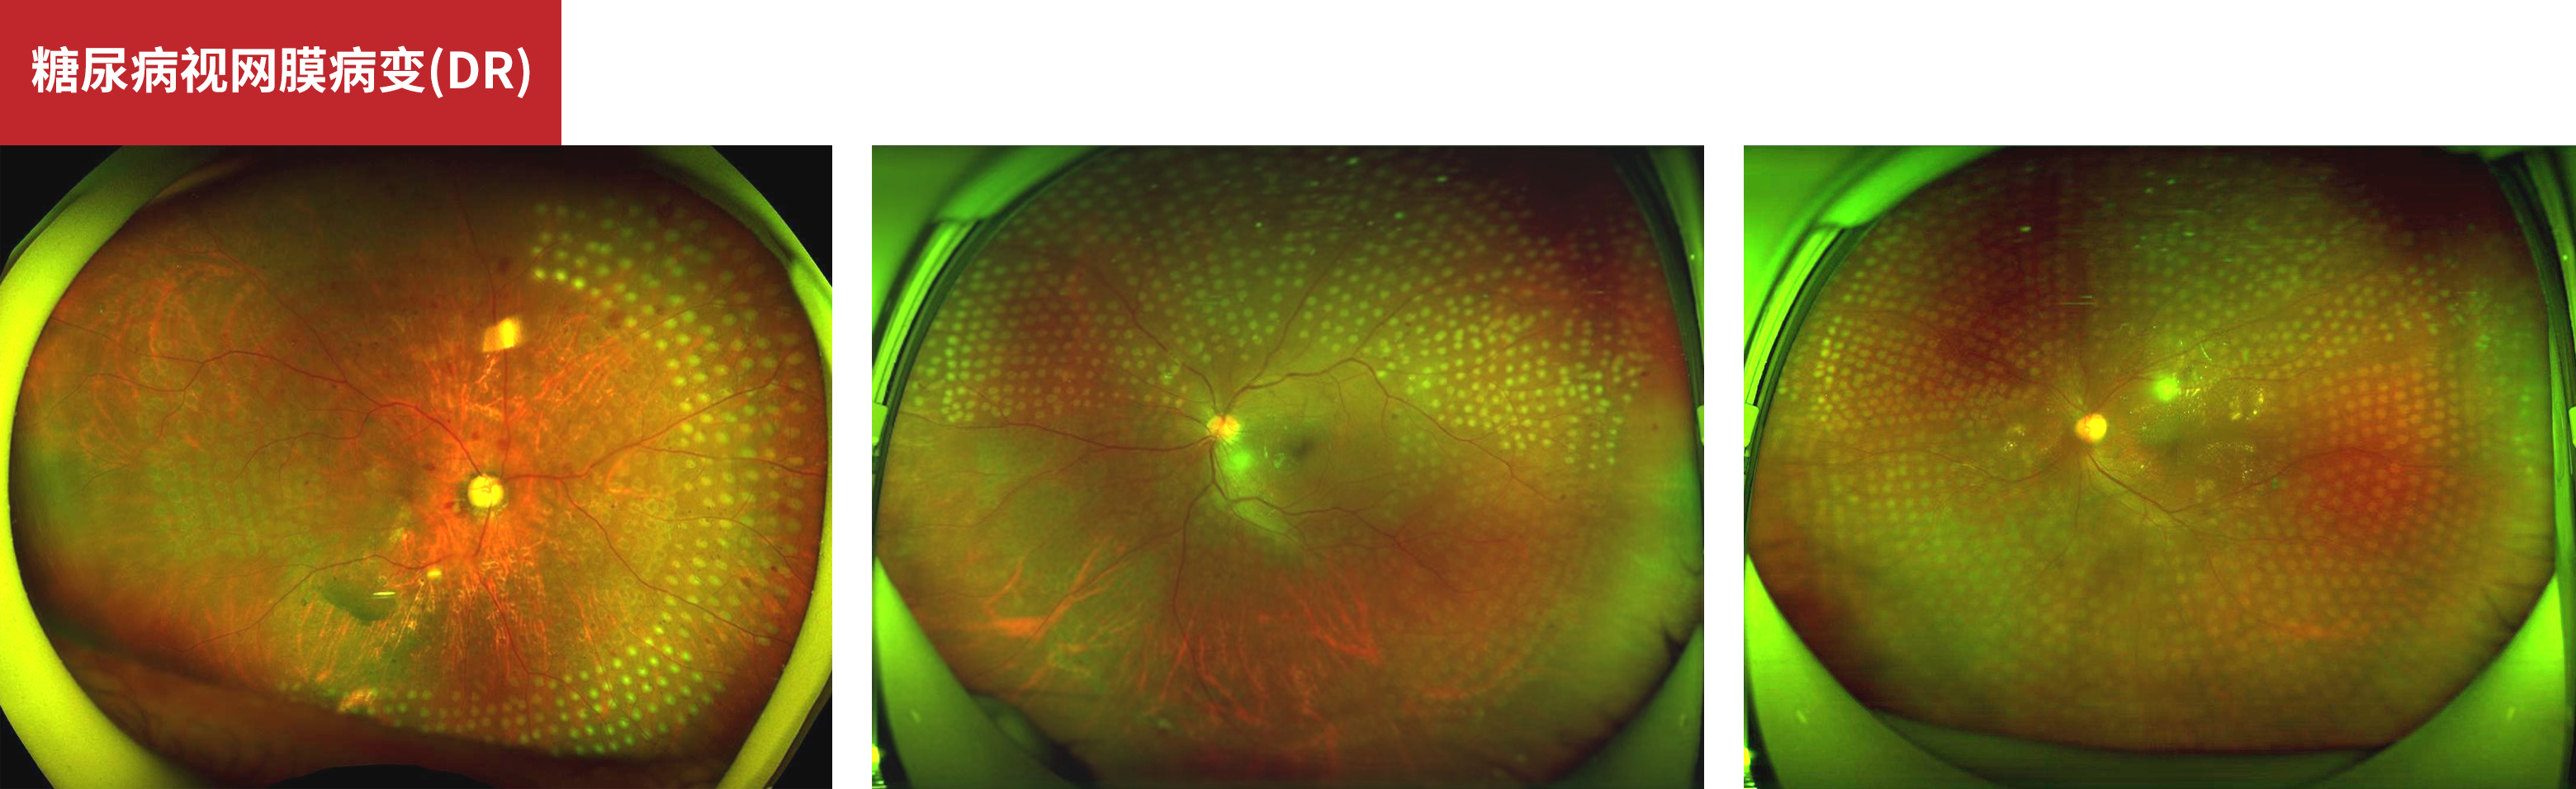

糖尿病视网膜病变(DR)

Pan Retinal Photocoagulation

鸣谢:哈尔滨爱尔眼科医院